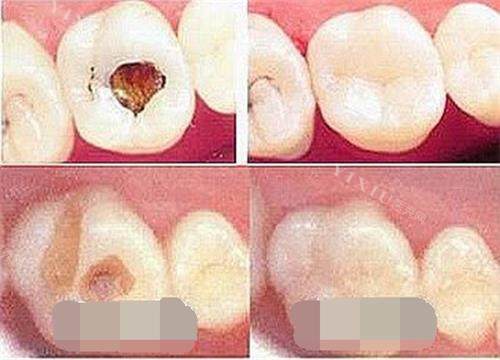

在牙齿治疗技术方面,柏瑞口腔采用常规治疗方法,针对龋齿、牙周病等常见口腔问题有标准化的处理方案。对于牙齿修复和种植,机构按照常规医疗规范进行操作。治疗过程中使用的材料符合行业标准。

补牙操作规范,使用常规材料